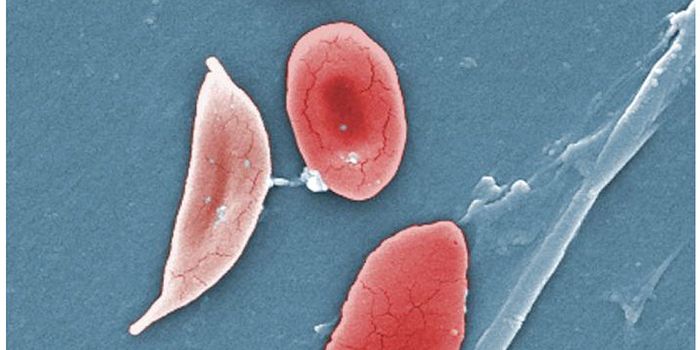

MAR 19, 2015Genetics & GenomicsA clinical trial of the most common sickle cell anemia drug, hydroxyurea, was halted a year early this winter because of ...